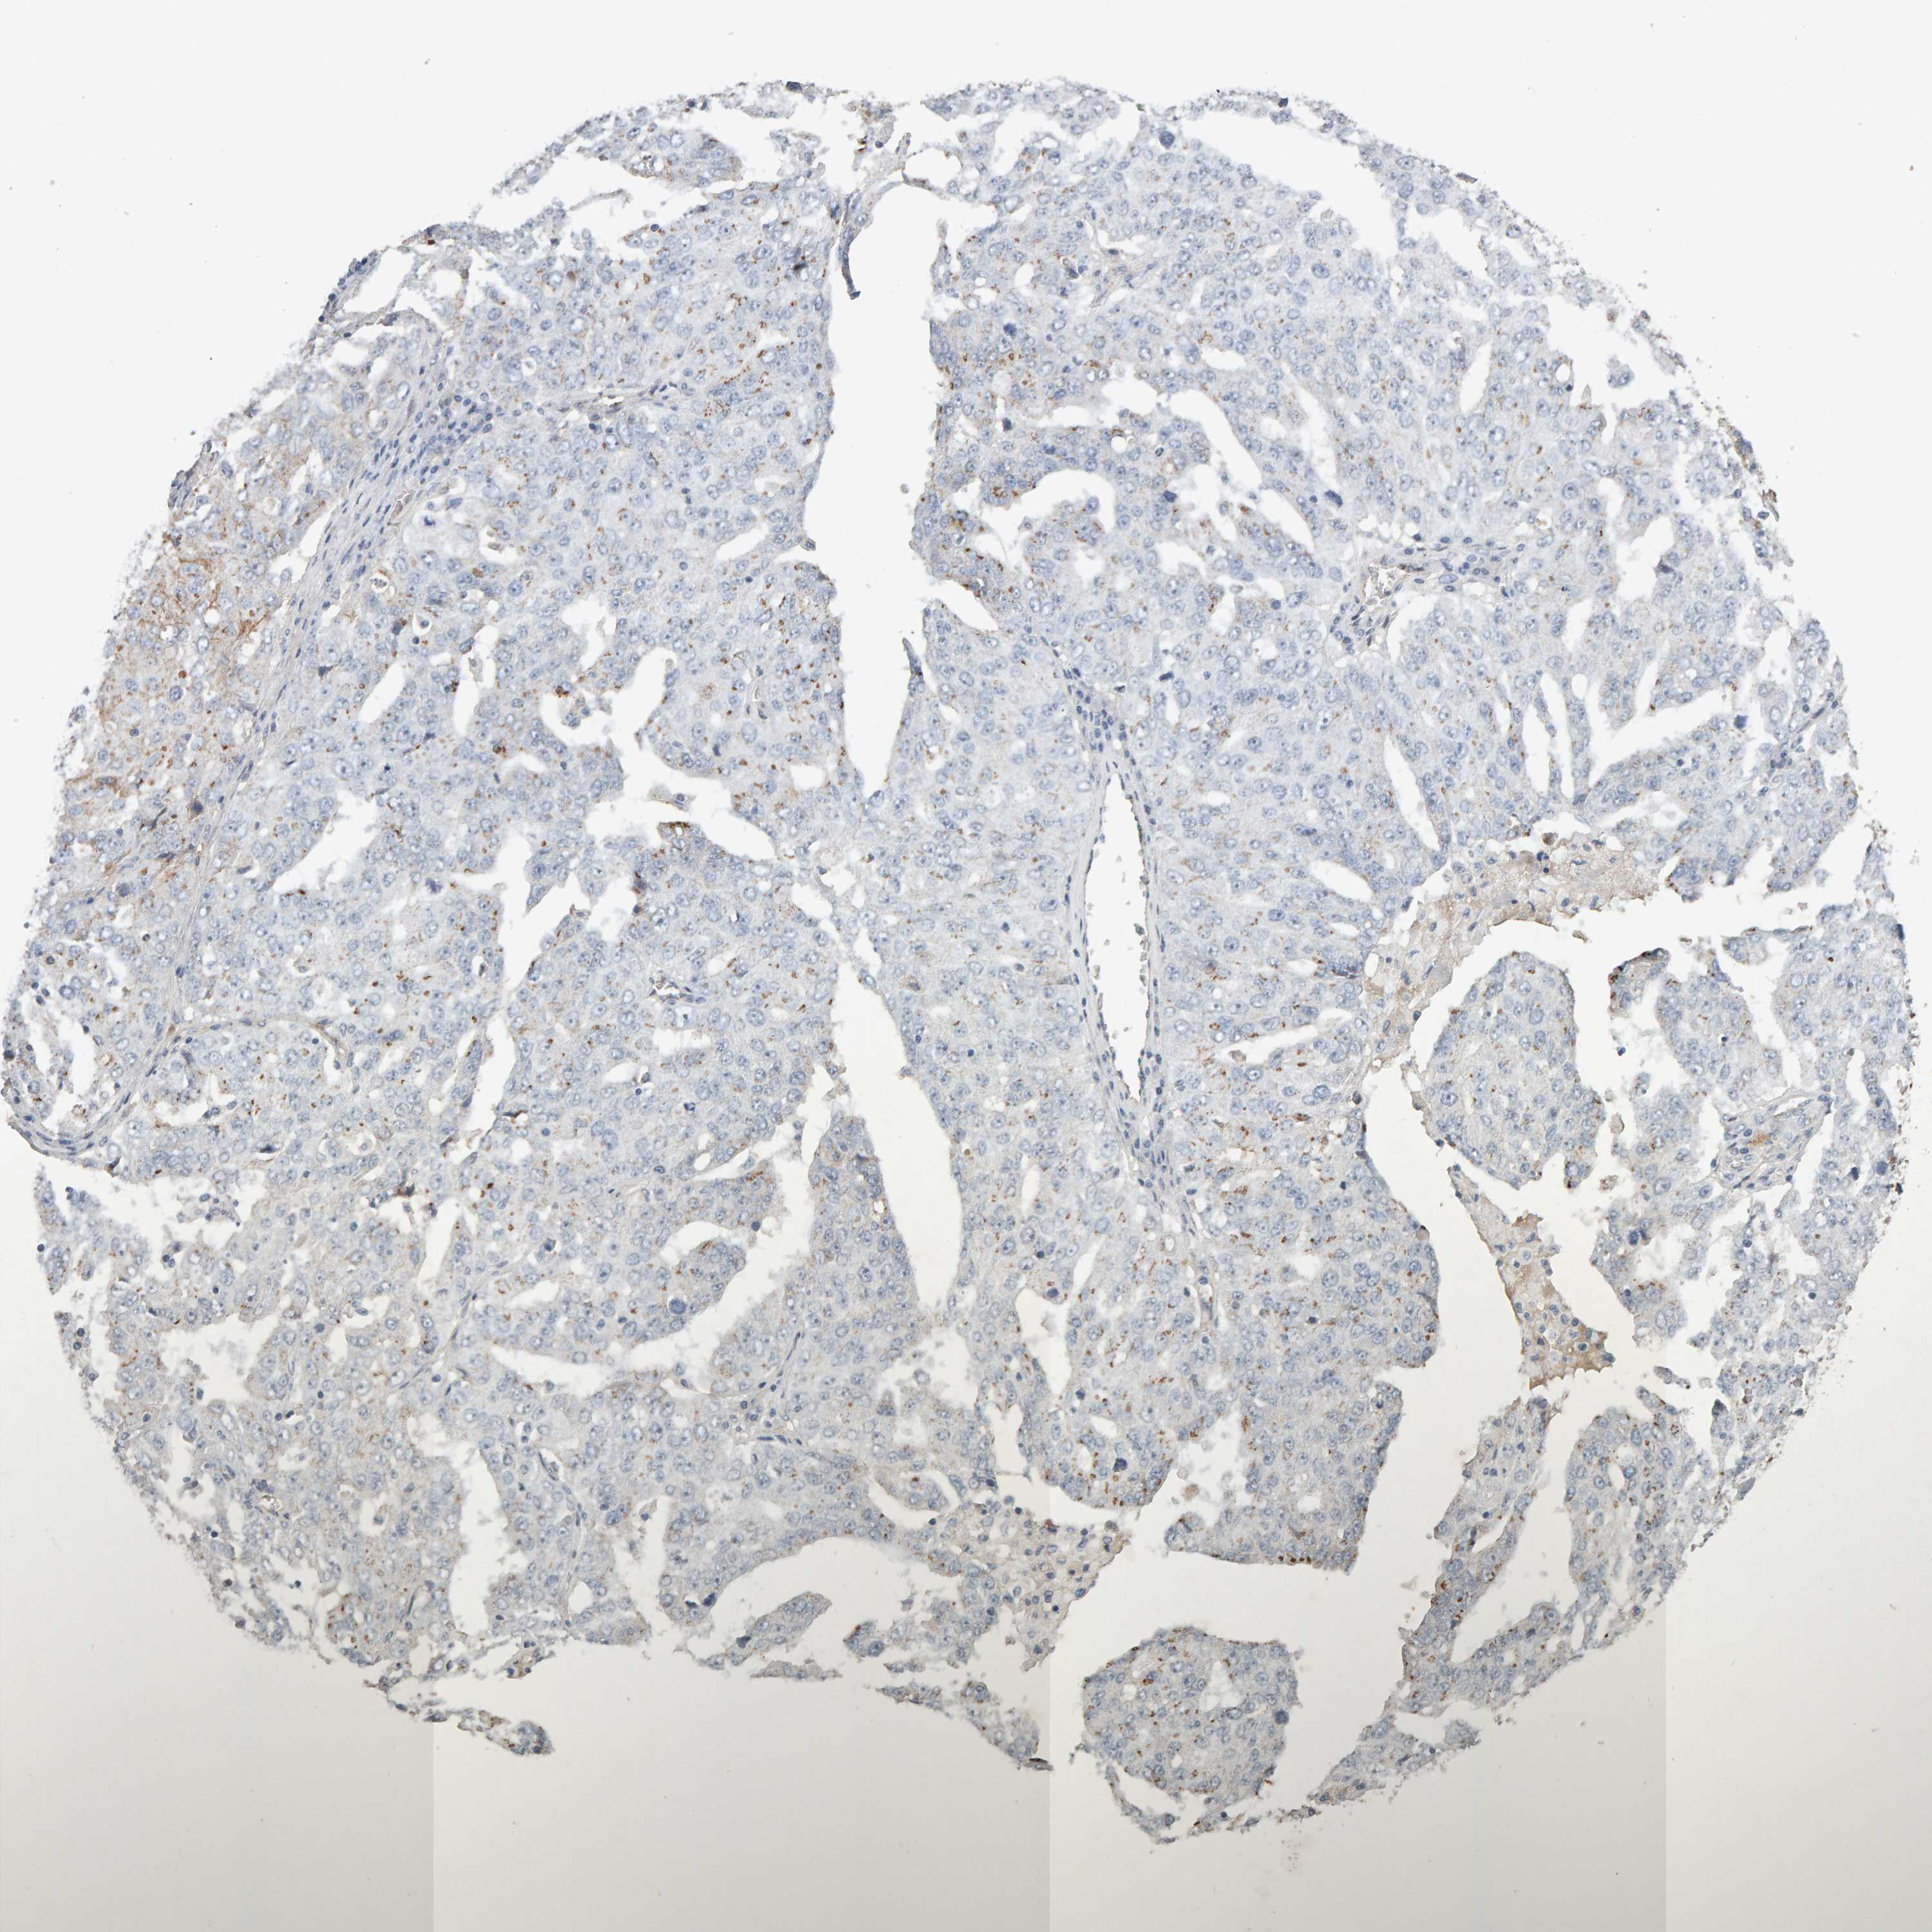

OVARIAN CANCER - Protein expressioni

A mouse-over function shows sample information and annotation data. Click on an image to view it in a full screen mode. Samples can be filtered based on level of antibody staining by selecting one or several of the following categories: high, medium, low and not detected. The assay and annotation is described here.

Note that samples used for immunohistochemistry by the Human Protein Atlas do not correspond to samples in the TCGA dataset.

Antibody stainingi

Antibody staining in the annotated cell types in the current human tissue is reported as not detected, low, medium, or high, based on conventional immunohistochemistry profiling in selected tissues. This score is based on the combination of the staining intensity and fraction of stained cells.

Each image is clickable and will lead to virtual microscopy that enables deeper exploration of all samples and also displays staining intensity scores, fraction scores and subcellular localization as well as patient and tissue information for each sample.

Antibody CAB022442

Antibody CAB022443

Staining

High

Medium

Low

Not detected

Intensity

Strong

Moderate

Weak

Negative

Quantity

>75%

75%-25%

<25%

None

Location

Nuclear

Cytoplasmic/membranous

Cytoplasmic/membranous,nuclear

Carcinoma, endometroid

Cystadenocarcinoma, serous, NOS

Cystadenocarcinoma, mucinous, NOS

Carcinoma, NOS